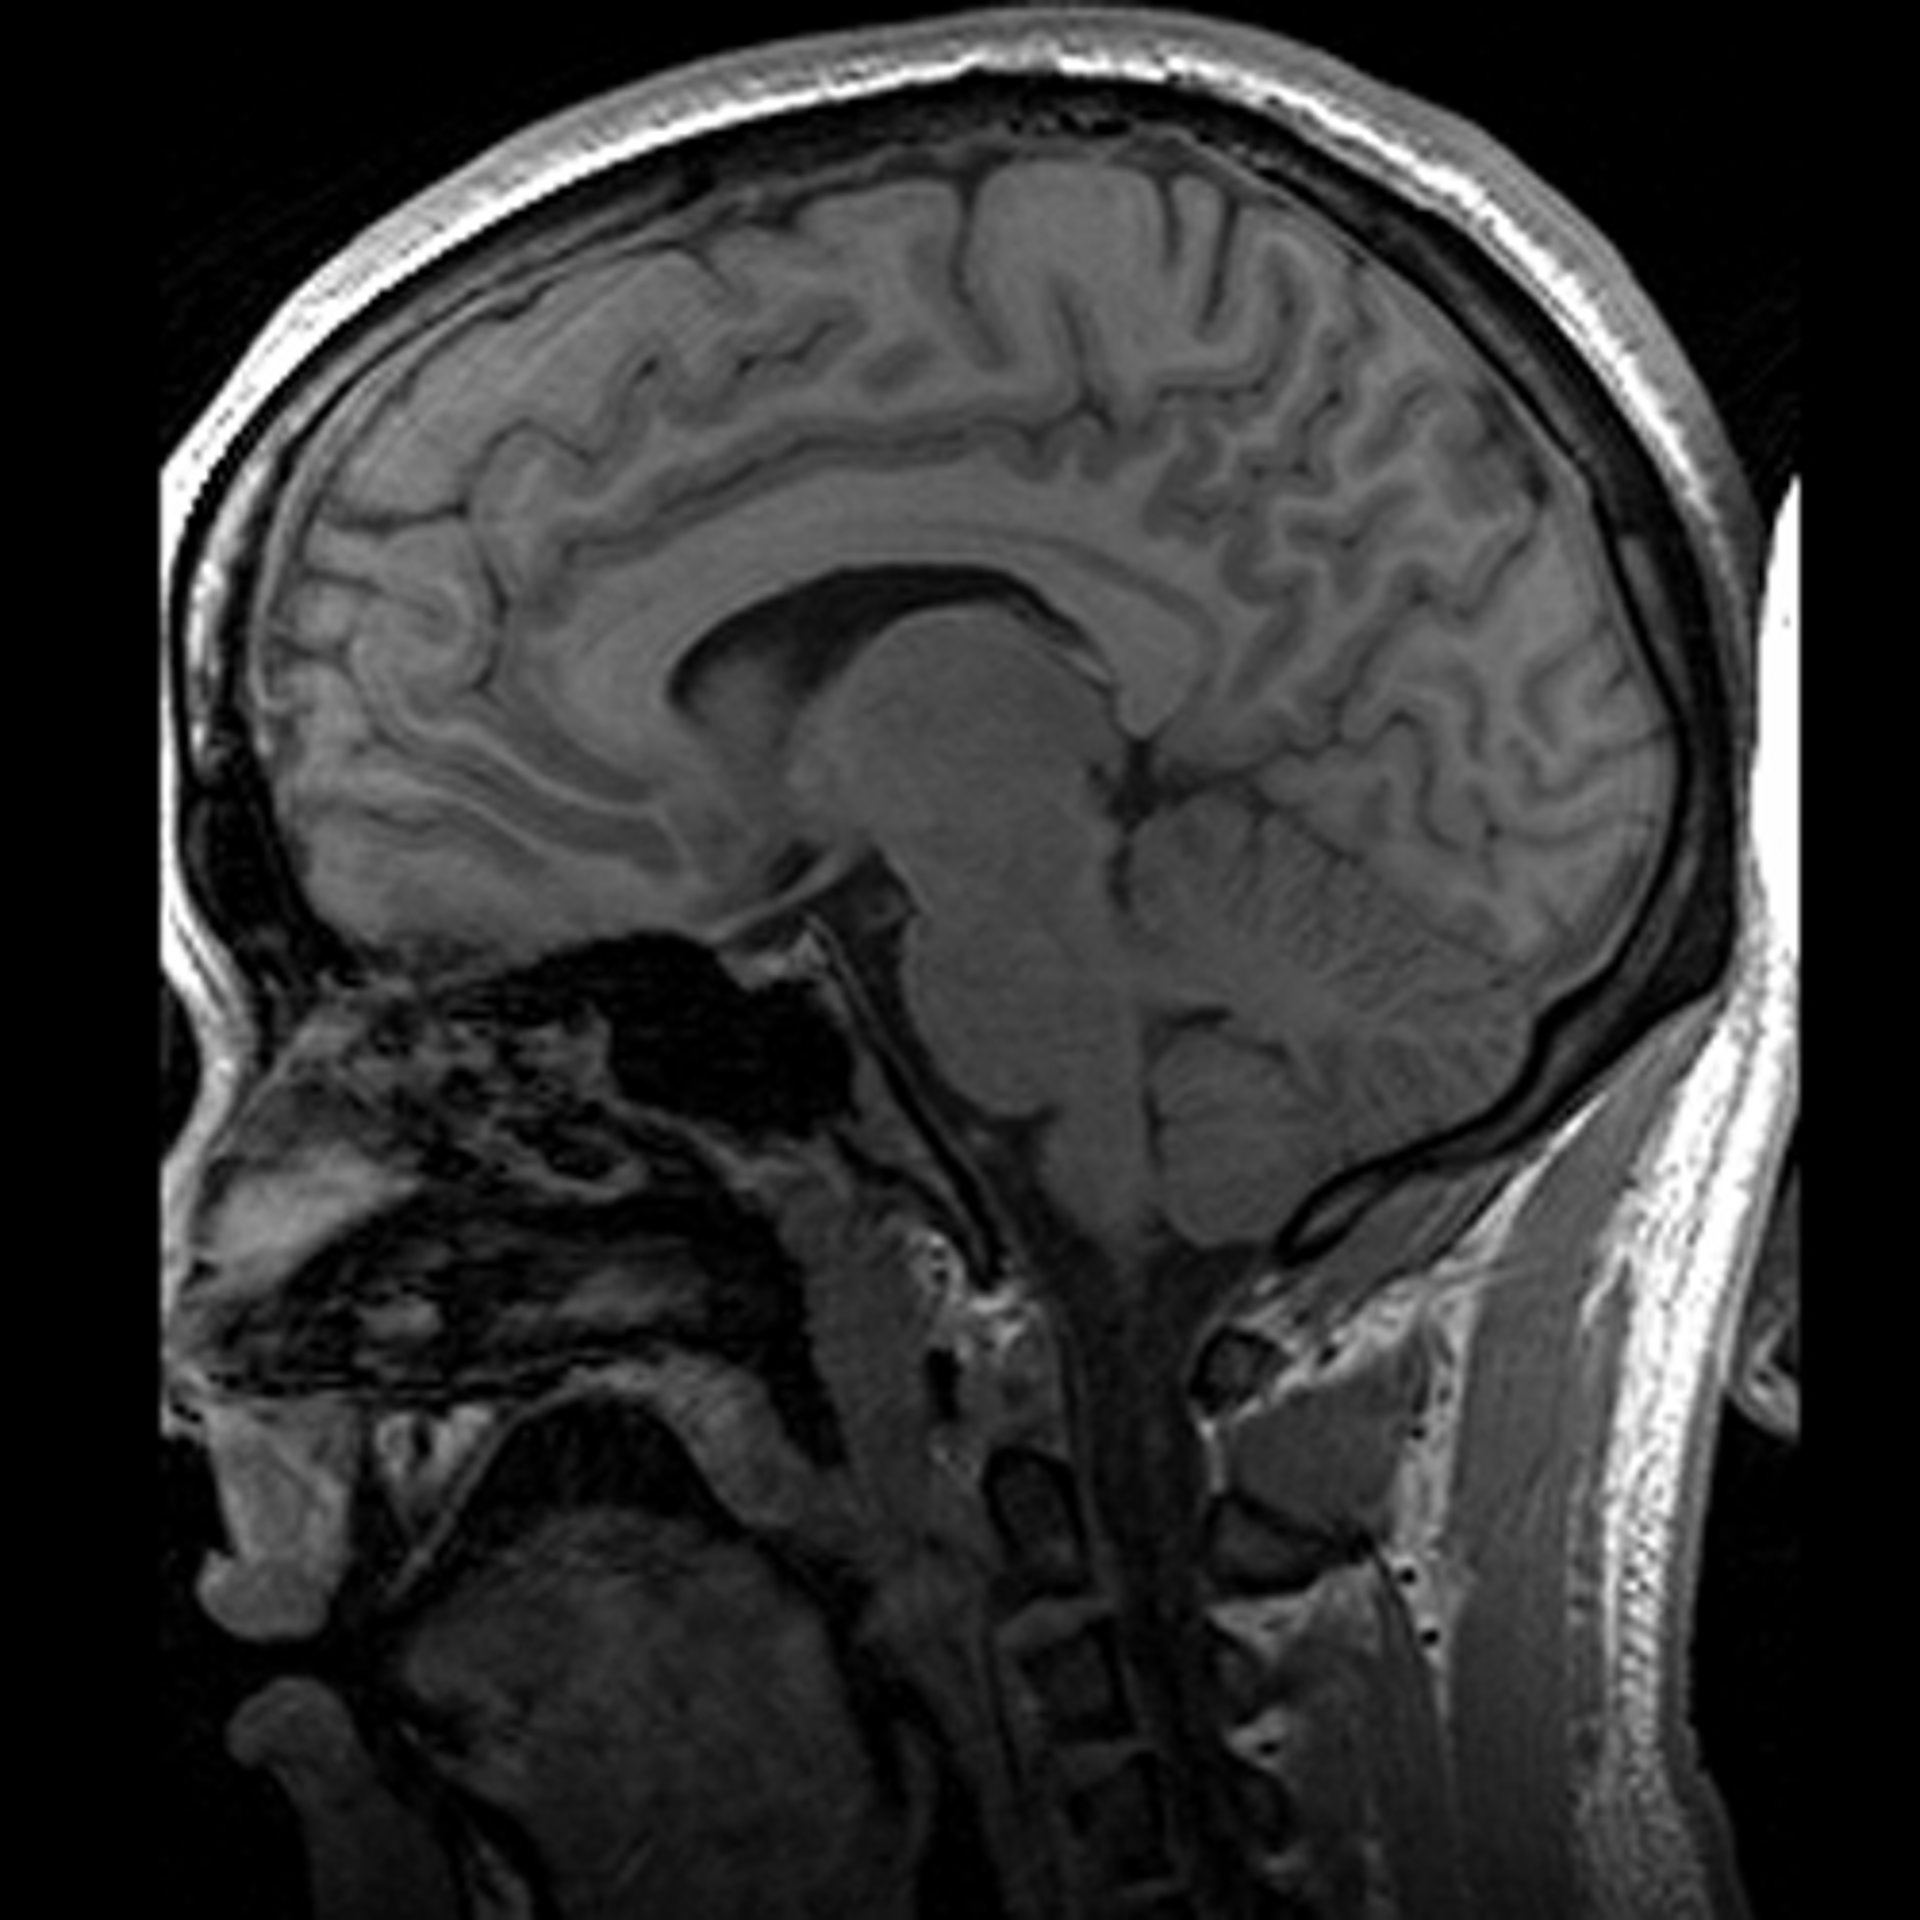

Un escáner cerebral para medir la capacidad de liderazgo

cerebro, escáner

DWAYNE REED/WIKIMEDIA COMMONS

Un equipo de neurocientíficos, psicólogos y expertos en Gestión de la Universidad de Reading, en Reino Unido, están colaborando en un estudio con el que pretenden averiguar si es posible detectar la capacidad de liderazgo de los ejecutivos mediante un escáner cerebral.

Para ello, una serie de directivos de empresas se han sometido a una resonancia magnética al tiempo que completan por ordenador una serie de ejercicios sobre decisiones financieras. "Lo que se les pide es que decidan si, en función de cierta información, es mejor tomar una decisión a corto o largo plazo", añade el profesor Douglas Saddy, que también colabora en el estudio.

De este modo, mientras el ejecutivo presiona el teclado se mide su actividad cerebral y, junto con el resultado de estas pruebas y otros escáneres, se intentarán extraer algunas conclusiones.